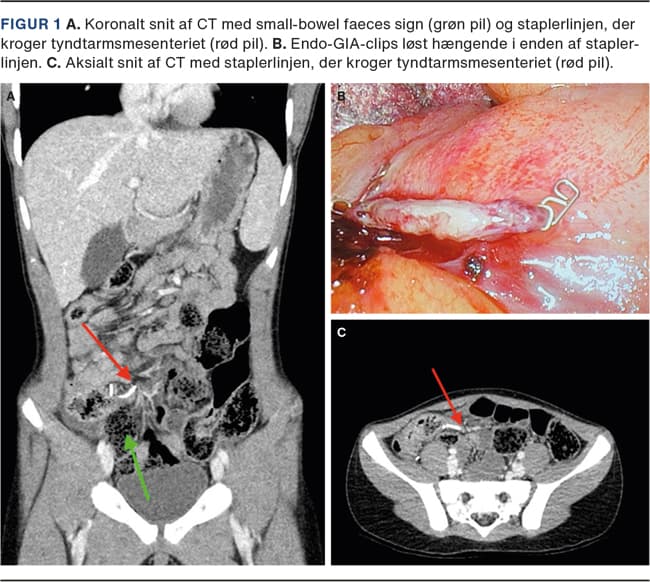

Laparoskopisk appendektomi er standardbehandling i Danmark for appendicitis acuta. Deling af appendix fra caecum gøres som regel ved endoloops eller en laparoskopisk stapler (endo-GIA), som sætter flere rækker af clips ved basis af appendix og deler skarpt imellem. Vi præsenterer her et tilfælde af tidlig postoperativ ileus på baggrund af adhærence af insufficient lukket clips fra staplerlinjen til tyndtarmsmesenteriet med intern herniering til følge.

En tiårig rask dreng fik foretaget laparoskopisk appendektomi for ukompliceret appendicitis acuta. En endo-GIA blev brugt til at dele appendix fra caecum. Patienten blev udskrevet kort efter operationen. Fem dage postoperativt blev han genindlagt med akut indsættende kraftige smerter i højre fossa iliaca med turevise forværringer, eksplosive opkastninger, manglende afføring gennem to dage og behandlingsrefraktære smerter. Klinisk fremstod han bleg og svært smertepåvirket. Ved palpation af abdomen fandtes diffus slipømhed, mest udtalt i højre fossa iliaca. Biokemi viste leukocytter på 20,6 × 109/l, C-reaktivt protein (CRP) 20 mg/l, laktat 3,9 mmol/l. Lavdosis-CT af abdomen viste dilaterede tyndtarmsslynger i det lille bækken med mulig overgangszone ved caecum. Der blev foretaget laparoskopi og fundet en delvist åben clips i den ene ende af staplerlinjen på caecum. Clipsen krogede sig ind i et segment af tyndtarmsmesenteriet (Figur 1). Den åbne clips sad yderligt i staplerlinjen. I tillæg var cirka to meter tyndtarm hernieret under clipsen og dannede en closed loop-konfiguration, defineret ved, at et tarmsegment afklemmes to steder i sit forløb, og fremstod med venøs stase i mesenteriet, uden nekroser. Adhærencen til clipsen blev delt skarpt, og afklemningen af tarmen var hermed ophævet. Tarmen observeredes, og der var hurtigt tegn til bedret blodforsyning. Tarmen var vital med peristaltik i hele sin længde, og der var ikke behov for resektion. Patienten var i klinisk bedring umiddelbart efter operationen og blev udskrevet samme døgn med mave-tarm-funktion og smertefrihed.